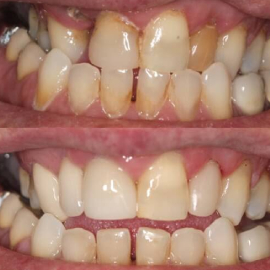

Ceramics can make a smile look nice again

Original bite position

Opened bite with upper restorations